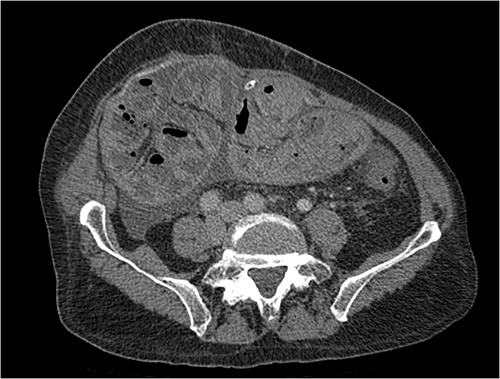

His clinical history and contrast-enhanced computed tomography (CT) findings (Figs 1–3) were compatible with EPS in Stage 4 (Table 2). Laboratory tests were non-specific, showing inflammation and malnutrition. He underwent nutritional support, corticosteroids and surgery. In surgery, fibrocollagenous membrane resection and enterolysis were done. Postoperative period was complicated by pneumonia treated with piperacillin+tazobactam and later bacterial peritonitis treated with ertapenem. The patient was discharged after 29 days with adequate nutrition and asymptomatic.

Portal phase transversal section image on CT showing loops wrapped in a membrane-like structure and thickened peritoneum.

Imaging exams, mainly CT are important to evaluate causes of bowel obstruction [4]. Dilated or non-dilated small intestine loops may be wrapped in a membrane-like structure, proximal bowel dilatation, thickened peritoneum with diffuse or local calcification, and loculated ascites are some of the findings on CT [1, 12]. Barium X-ray provides a clue to bowel encapsulation, showing clustered loops of the small intestine in the center of the abdomen, known as the cauliflower sign [4]. Ultrasound and magnetic resonance imaging may give a clue but are rarely used [1, 12].